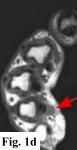

MRI FINDINGS:   MRI was performed on AIC's high-field 1.5 Tesla short-bore Siemens Symphony scanner using a small flexible surface coil. Fig. 1a is a high-resolution coronal DESS, Fig. 1b a sagittal T1 weighted, Fig. 1c a sagittal turbo STIR, and Fig. 1d an axial T1 weighted. They demonstrate a 5x5x7 mm nodule in the volar aspect of the hand at the level of the 4th MCP joint inseparable from the flexor digitorum superficialis tendon (arrows) with some adjacent soft tissue edema. The underlying tendon and bones are otherwise intact.